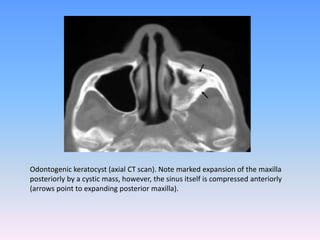

CT :

Ct scan in case of diagnosis of okc of large mandible and cysts

and tumors of maxlla particularly where extension of the

lesion to the cranial base is suspected .(Voorsmit)

Important features of this technique :-

1. Lack of image superimposition

2. Preservation of soft tisuue detail

3. Selective enlargement of area of interest

4. High degree of accuracy and possibility of three

dimentional interpretation.

Odontogenic keratocyst (axial CT scan). Note marked expansion of the maxilla

posteriorly by a cystic mass, however, the sinus itself is compressed anteriorly

(arrows point to expanding posterior maxilla).